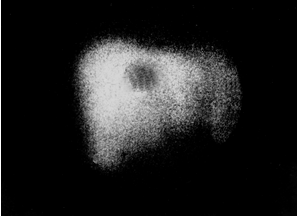

При сцинтиграфии накопления радиофармпрепарата может значительно снижаться в отдельных областях или диффузно во всем органе. Наличие ”холодных” очагов (рис. 11) является признаком объемных образований (опухоль, метастаз, киста, абсцесс).

Гепатосцинтиграмма. Определяется ”холодный” очаг – опухоль.